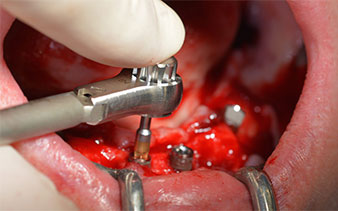

The mental foramen was first identified as a limiting anatomical structure and then the cortical bone of the crest was smoothed with the straight handpiece and a large rose-head bur (Fig. 4).

residual dentition

Fig. 4

The surgical protocol for the implants employed (SKY, bredent medical) specifies a speed of 1,200 rpm for the pilot drilling (Fig. 7 - 9).

Fig. 7

speed of 1,200 rpm

Fig. 8

Fig. 9

This corresponds to the next preset position in the Implantmed. Here we see the W&H contra-angle handpiece being held at a 45° angle to mesiocaudal in the region of 45 in order to preserve the mental nerve. The mental foramen is used as the anatomic reference for all drilling in this region. The subsequent holes were drilled at a reduced speed of 300 rpm (Fig. 10 and 11).

W&H contra-angle

Fig. 10

speed of 300 rpm

Fig. 11